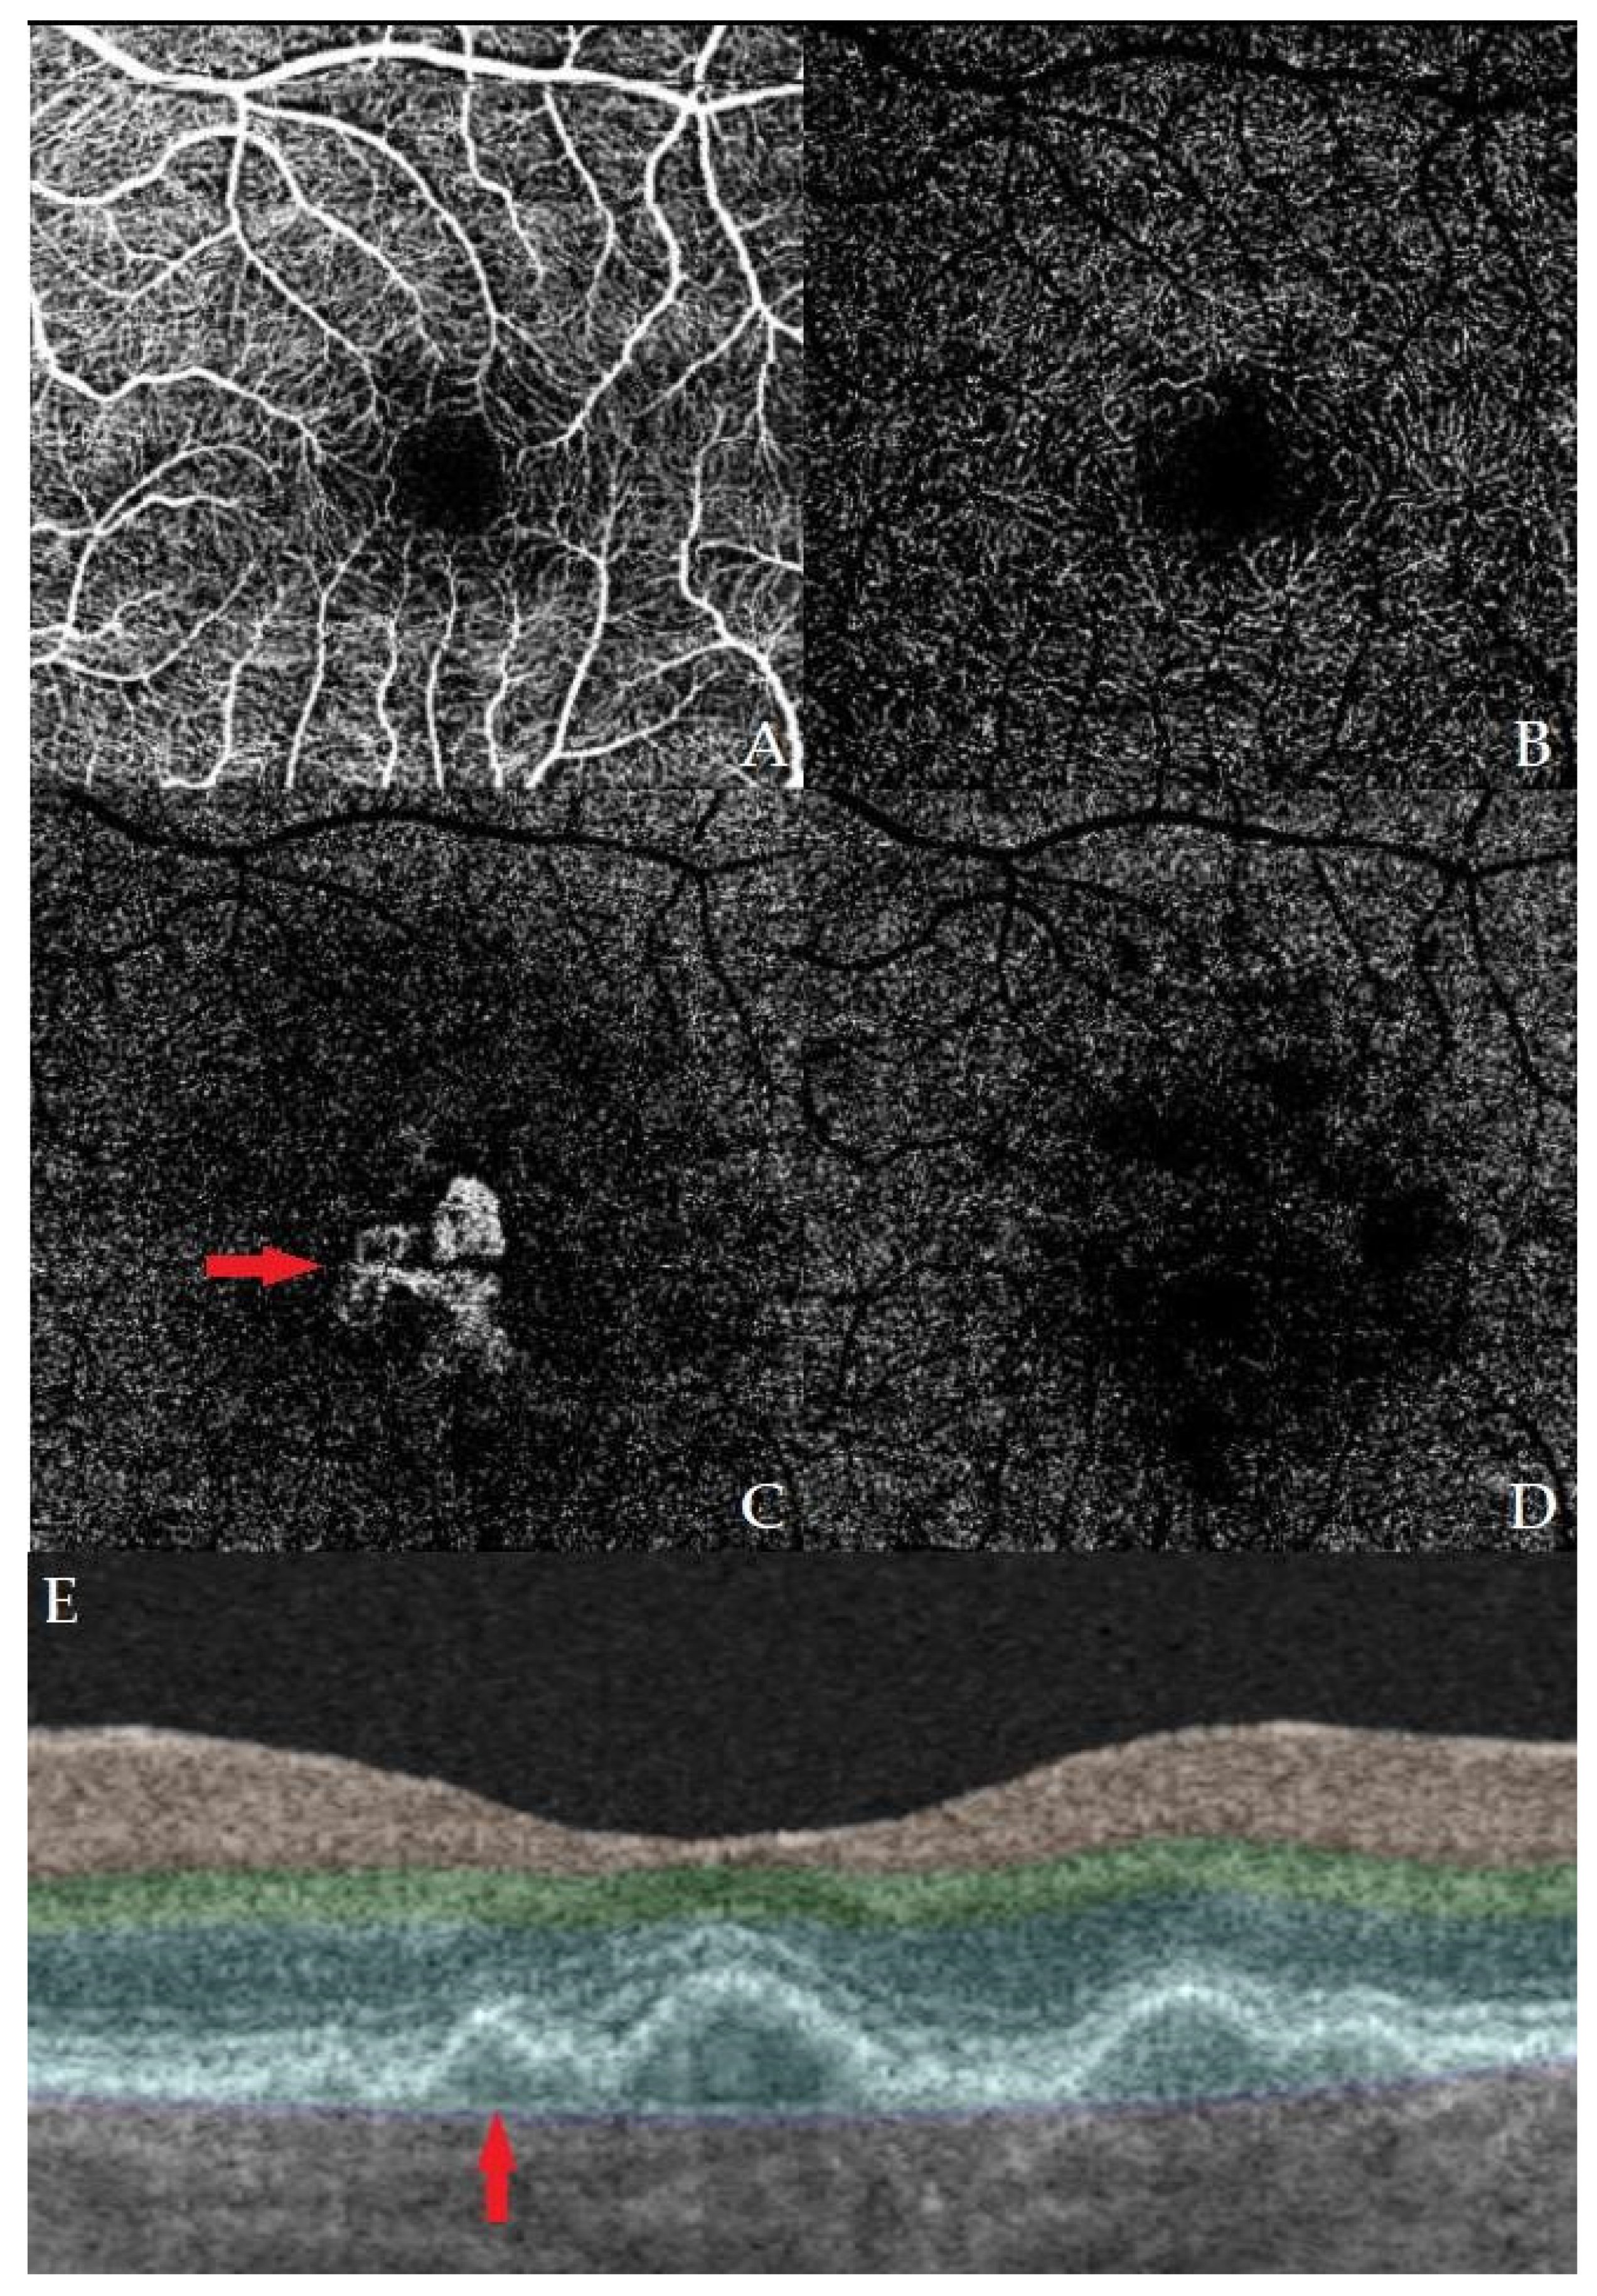

Correlation of the OCT Double-Layer Sign with Type 1 Non-Exudative Neovascularization on OCT-A in Age-Related Macular Degeneration

- Shi, Y.; Motulsky, E.H.; Goldhardt, R.; Zohar, Y.; Thulliez, M.; Feuer, W.; Gregori, G.; Rosenfeld, P.J. Predictive Value of the OCT Double-Layer Sign for Identifying Subclinical Neovascularization in Age-Related Macular Degeneration. Ophthalmol. Retina 2019, 3, 211–219. [Google Scholar] [CrossRef]